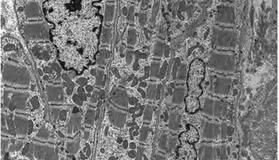

溶酶体